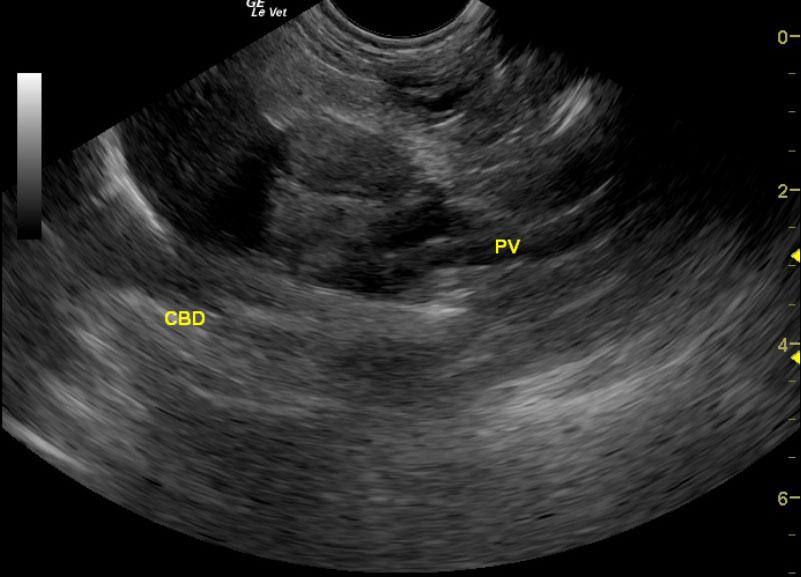

A 12-year-old FS Pomeranian was presented for acute vomiting and diarrhea. On physical examination, dyspnea, coughing, and a heart murmur were present. Urinalysis, T4, coagulation profile, and CBC were all within normal limits. Abnormalities on serum biochemistry were revealed elevated total proteins, globulin, liver enzyme activity, total bilirubin, and azotemia.